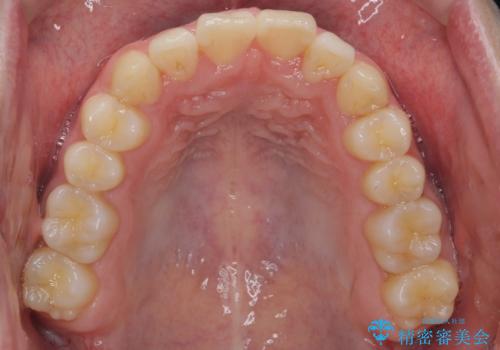

- 前歯のがたつきを主訴に来院。

左下の奥歯を後ろに移動して、中に入ってすれちがっていた小臼歯を並べました。

奥歯を後ろに移動させるために、矯正用のミニスクリューを用いました。(インプラント矯正)